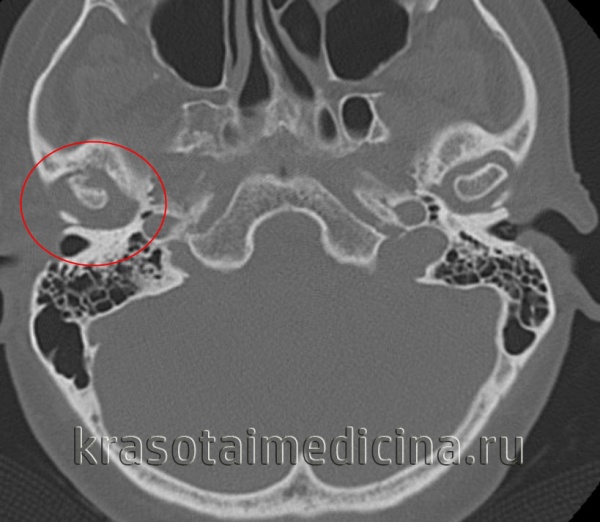

(Справа) На аксиальной КТ без КУ у этого же пациента определяется склероз и увеличение всех размеров мыщелка со слиянием с височной костью. Суставное пространство не визуализируется.